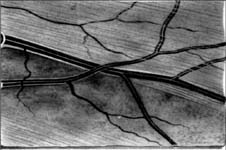

Výpadek nervových vláken začíná temporálně dole, kde je na terči patrný zálom vény. Na barevné fotografii není viditelný, protože se jedná o výpadek v hlubší vrstvě nervových vláken, která je překryta vlákny neporušenými. Tato hluboká vlákna směřují do temporální dolní části makuly a v zorném poli jim odpovídá horní nasální skok.